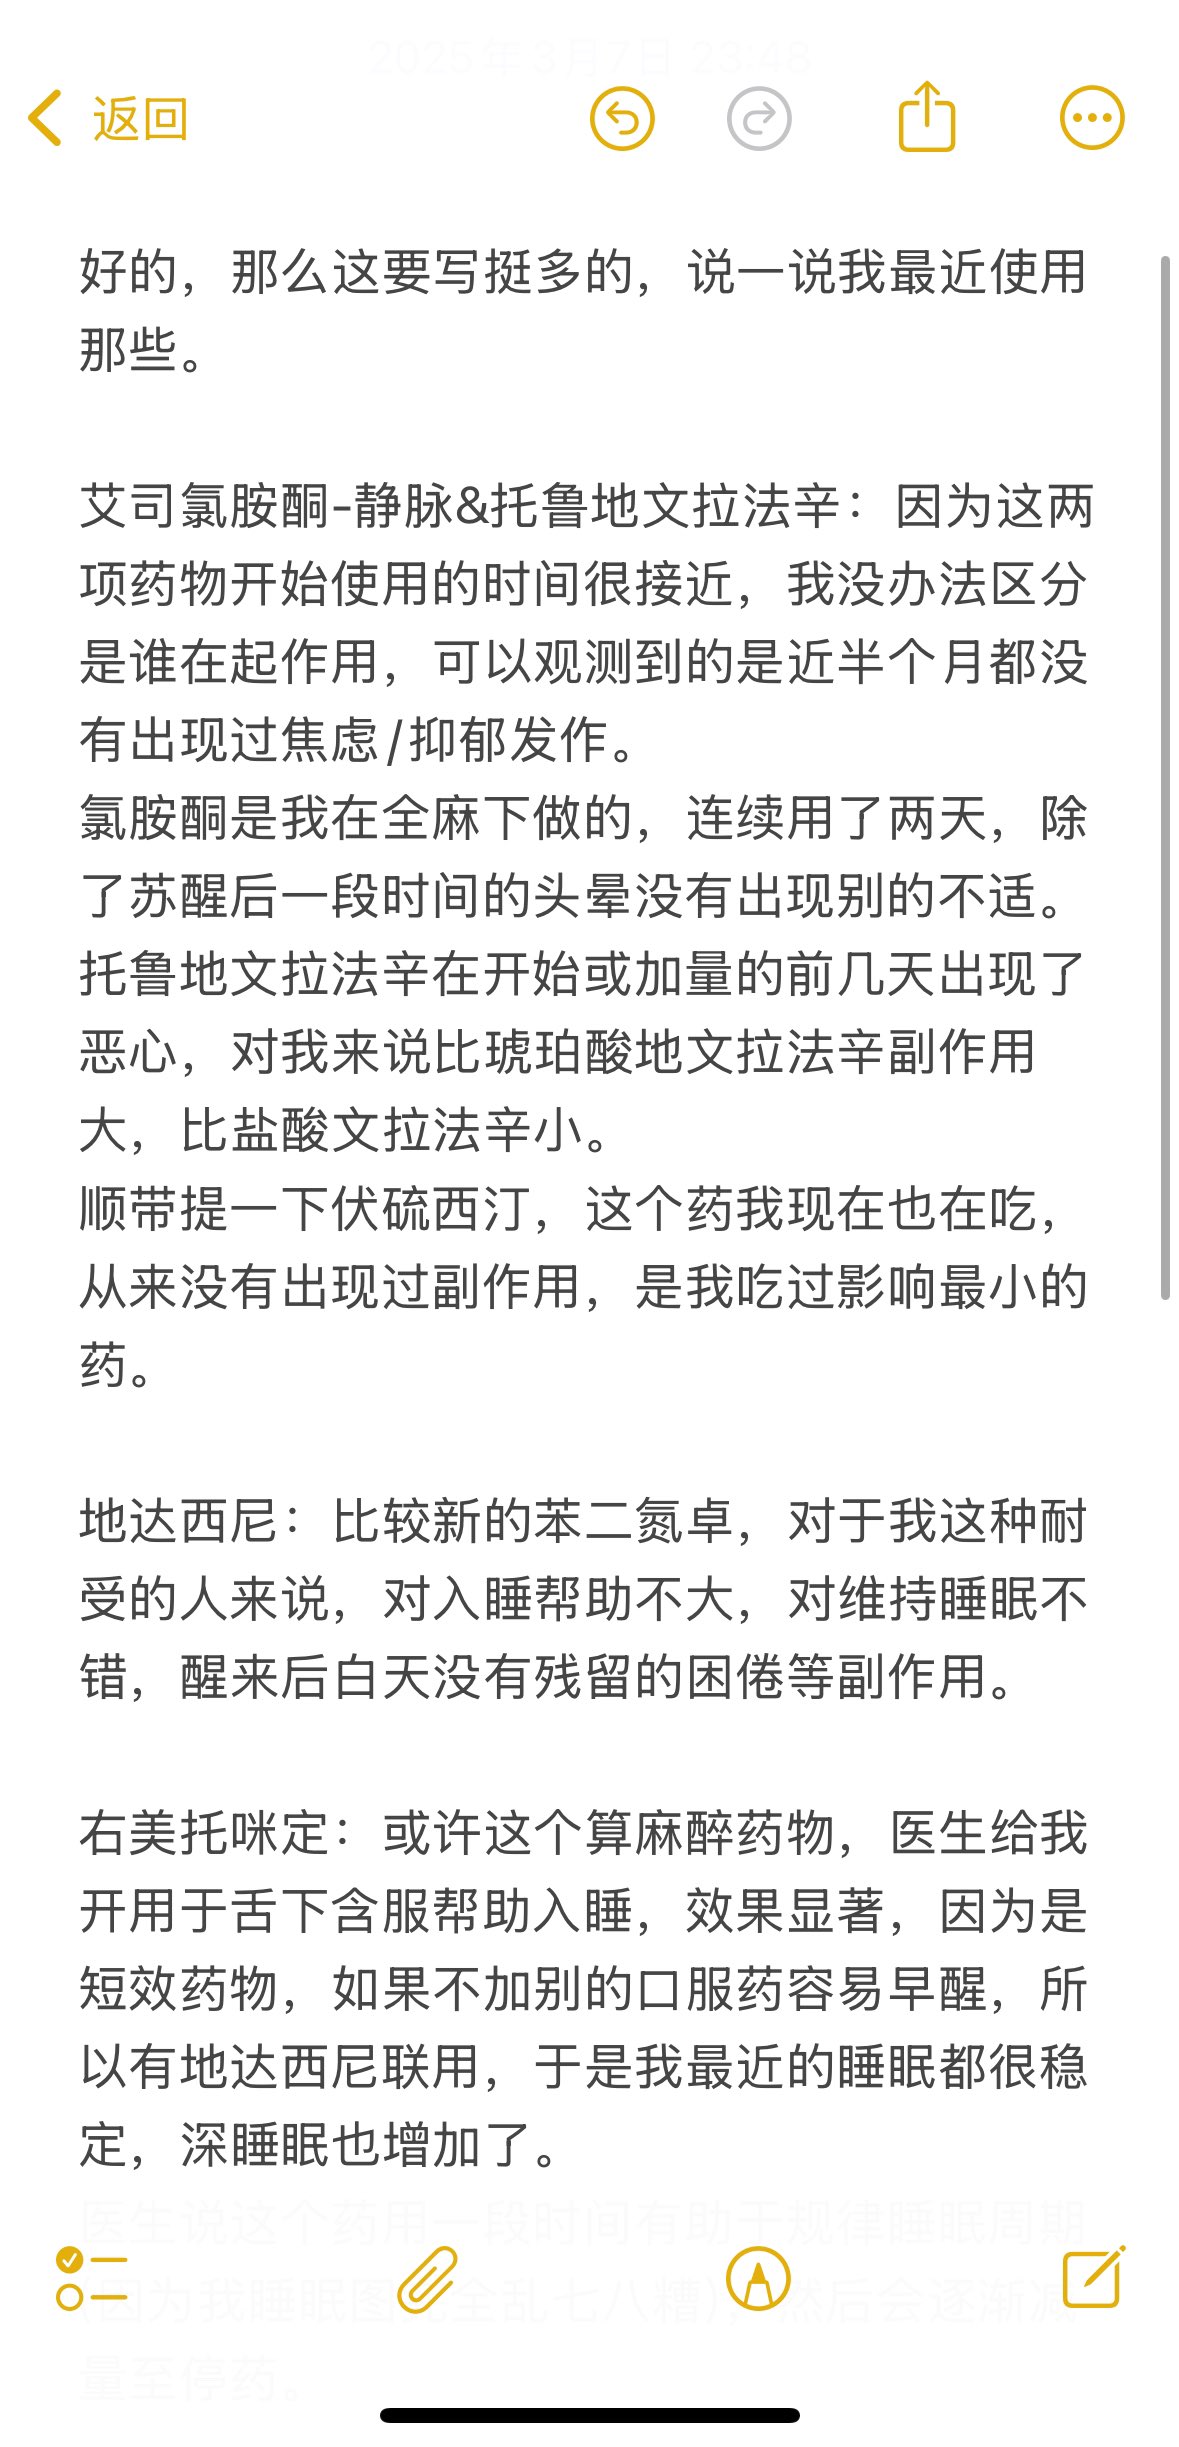

2024-08-14 11:34:53 UTC

甚至在第二天有余晖的感觉,虽然发生了很多破事但没怎么影响心情*抗焦虑&镇静

运动协调性稍差,表现为走路和站立时平衡不好

此剂量下对睡眠的改善作用,增加了慢波睡眠且没有影响rem,精力恢复+

FDA数据,在临床剂量下(75-600mg)普瑞巴林的依赖性低于bzd,并相比之下它产生的认知和精神运动障碍较轻 https://t.co/TJ7ZOQ7pbC